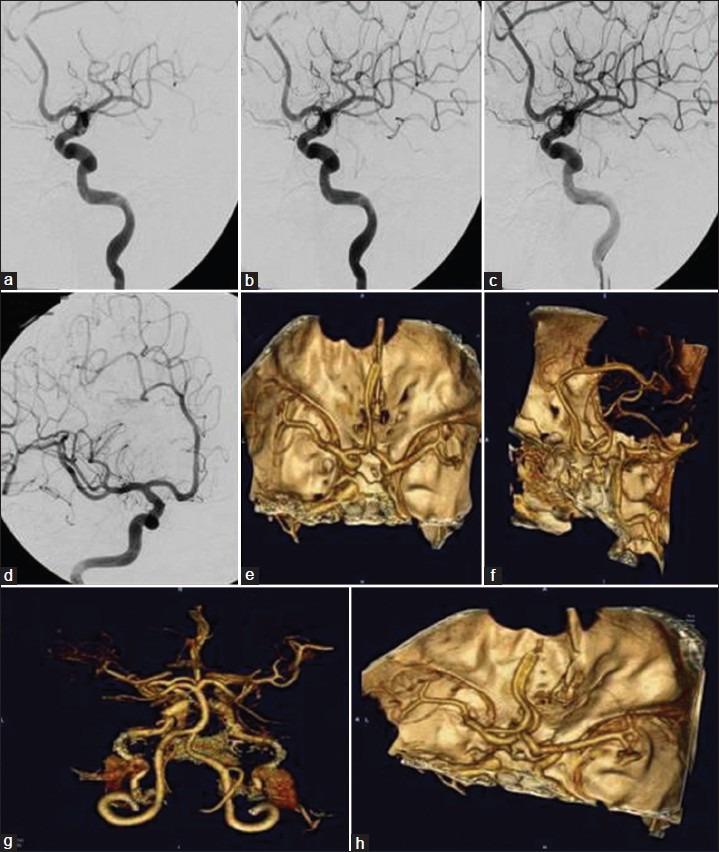

CASE DESCRIPTION

We describe the unique case of a 47-year-old female who developed multiple FIAs over a 6-year period without an obvious underlying pathology. The patient's medical history was significant for obesity, migraine headaches, insomnia, breast cancer, and chronic skin rash. Various diagnoses were explored including infectious etiologies, autoimmune vasculopathies, malignancy-related causes, connective tissue disorders, and underlying genetic conditions. However, all investigations, including aneurysm wall and skin biopsies were negative or deemed noncontributory toward making a definitive diagnosis.

病例描述

我们描述了一名47岁女性的独特病例,该患者在6年时间里出现了多个FIAs,且无明显潜在病理情况。患者的病史包括肥胖、偏头痛、失眠、乳腺癌和慢性皮疹。对各种诊断进行了探索,包括感染性病因、自身免疫性血管病变、恶性肿瘤相关病因、结缔组织疾病和潜在遗传疾病。然而,所有检查,包括动脉瘤壁和皮肤活检均为阴性或被认为对明确诊断无帮助。